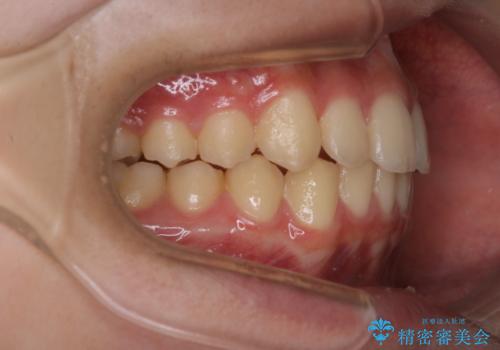

非抜歯で劇的に出っ歯を改善!インビザラインとカリエールの組み合わせ治療

- インビザライン カリエール

- 患者様、出っ歯のお悩みで来院されました。

骨格の分析を行ったところ上顎も出てはいるのですが、下顎が引っ込んでいる状態であるということがわかりました。

よって上顎の歯を抜いて治療をするのではなく、カリエールという器具を使用して下顎を前に引っ張り出しながら上顎を引っ込めるという治療を行うことにしました。